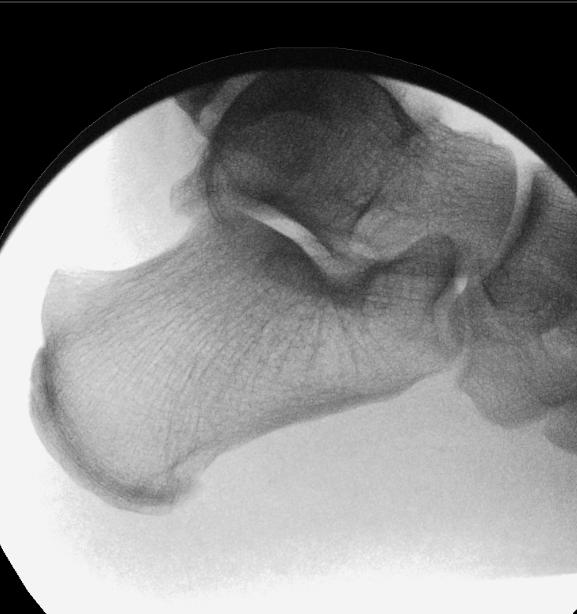

Mildly displaced posterolateral fragments are selected (Haraguchi 1, Mason 1, 2A and Bartonicek 1, 2). Pre-operative CT is obtained to assess the posterior malleolus fracture and screw trajectory.

The patient is positioned in a lateral position with the injured side up and on an elevating block, placed behind the non-operative leg. This gives a lateral view of the ankle and allows external rotation of the hip to enable mortise view fluoroscopy, access to the anterior ankle for trauma scope and access medially for medial malleolus fixation. Anatomy is marked on the skin using image intensifier and the level of incision is planned to approach the posterior malleolus.

The posterior malleolus should be fixed first to enable proper assessment of joint line and fracture fragment reduction. Once medial and lateral metalwork is in situ this will obscure fluoroscopic assessment of the posterior malleolus. If fibula reduction is required to restore the syndesmosis prior to posterior fixation the fibula can be approached through a direct lateral approach in this position, reduced and held with a clamp or K-wire in a manner that doesn’t obscure fluoroscopic assessment.

A 10mm incision on the lateral edge of the Achilles tendon at the level of the

posterior malleolus and a 10mm tunnel is blunt dissected down to bone using long dissecting scissors. The leg is rotated until the X-ray projection of the posterior malleolus cortex is separate to the posterior cortex of the fibula. A radiolucent depth gauge or 2mm syringe barrel is used as a wire guide to protect the soft tissues. A guidewire is placed on the posterior malleolus cortex by feel and the leg rotated until there is no overlap between cortex and wire to help judge the exact position in relation to the fracture

and to check the wire is on the tibial cortex and not the fibula.

The guidewire is passed into the fragment and the position is checked on the AP image. The fibula is reduced into the incisura with thumb pressure. The leg is then rotated until the fracture plane is visible on fluoroscopy. The depth gauge/ syringe and guidewire are used to joystick the fragment into position and the wire is passed across the fracture. If the fragment requires further inferior translation

the wire can be angled inferiorly so that screw compression will translate the fragment distally. Once the wire is across the fragment, the depth gauge is pushed against the posterior malleolus to check the fragment will compress. Wire position is checked on the mortise view with depth gauge or artery clip against the posterior tibial cortex to assess the exact entry point, ensuring it will not irritate the fibula or syndesmosis.

The near cortex only is drilled, and one unicortical 4mm cannulated partially threaded screw and washer is inserted under image intensifier. As the washer meets the posterior malleolus it should angle to meet the cortical contour of the posterior malleolus, further confirming correct positioning, and the fracture should be seen to compress. If the wire has been angled inferiorly the fragment should reduce more distally by 1mm or so. Final checks are performed, and the percutaneous portal can be closed with skin suture alone. The surgeon is then free to complete necessary fixation of the malleoli and syndesmosis through direct approaches. n